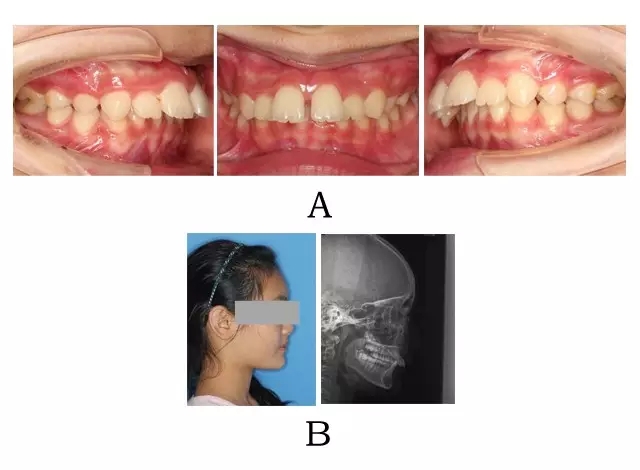

面型前突,唇態(tài)較正常,而下部高度不足、頦唇溝較深,下頜平面較平坦??趦缺憩F上頜正常或伴輕度齒槽性前突,上前牙輕度唇傾。下頜后退,嚴重的深覆合深覆蓋,磨牙關系常為遠中關系,尖-尖咬合(圖 3-1)。

圖 3-1:頜位性突面畸形臨床表現及頭顱側位影像特征。

(A)齒槽與牙列特點 (B)側貌與影像對比

Figure 3-1. Clinical manifestation and cephalometric image for mandibular positional prognathism. (A) Alveolar and dentition specifics. (B) Facial profile and radiographic image.